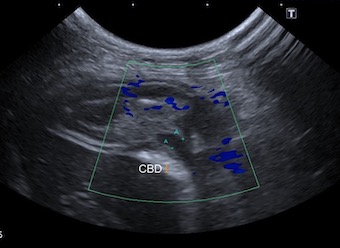

超音波検査画像です。

胆嚢の中に「キウイフルーツパターン」というキウイフルーツのような模様が見えた時、胆嚢粘液嚢腫を強く疑います。

総胆管の拡張も認められ、十二指腸の開口部で閉塞を起こしている可能性が考えられました。